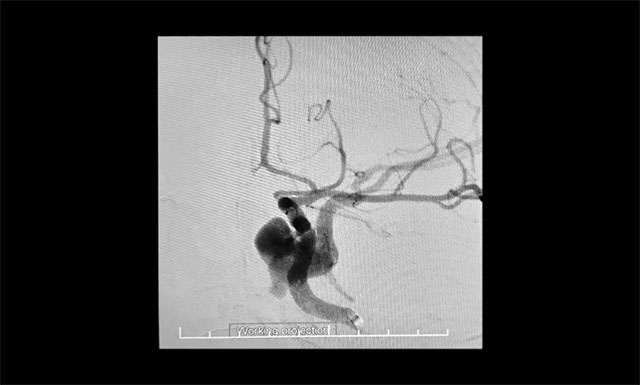

▲ DSA 檢查確診:左側(cè)頸內(nèi)動(dòng)脈海綿竇瘺

頸動(dòng)脈3D造影提示,左側(cè)頸內(nèi)動(dòng)脈海綿竇瘺,瘺口位于頸內(nèi)動(dòng)脈破裂孔段內(nèi)后方,瘺口處假性動(dòng)脈瘤形成,血液向左側(cè)側(cè)裂靜脈及左側(cè)巖下竇上方引流,瘺口小,流量大,屬于難治性頸內(nèi)動(dòng)脈海綿竇瘺。綜合患者病情,張琪主任決定實(shí)施球囊保護(hù)聯(lián)合封堵手術(shù)。該手術(shù)手術(shù)操作繁瑣,技術(shù)難度較大、對(duì)術(shù)者要求很高。